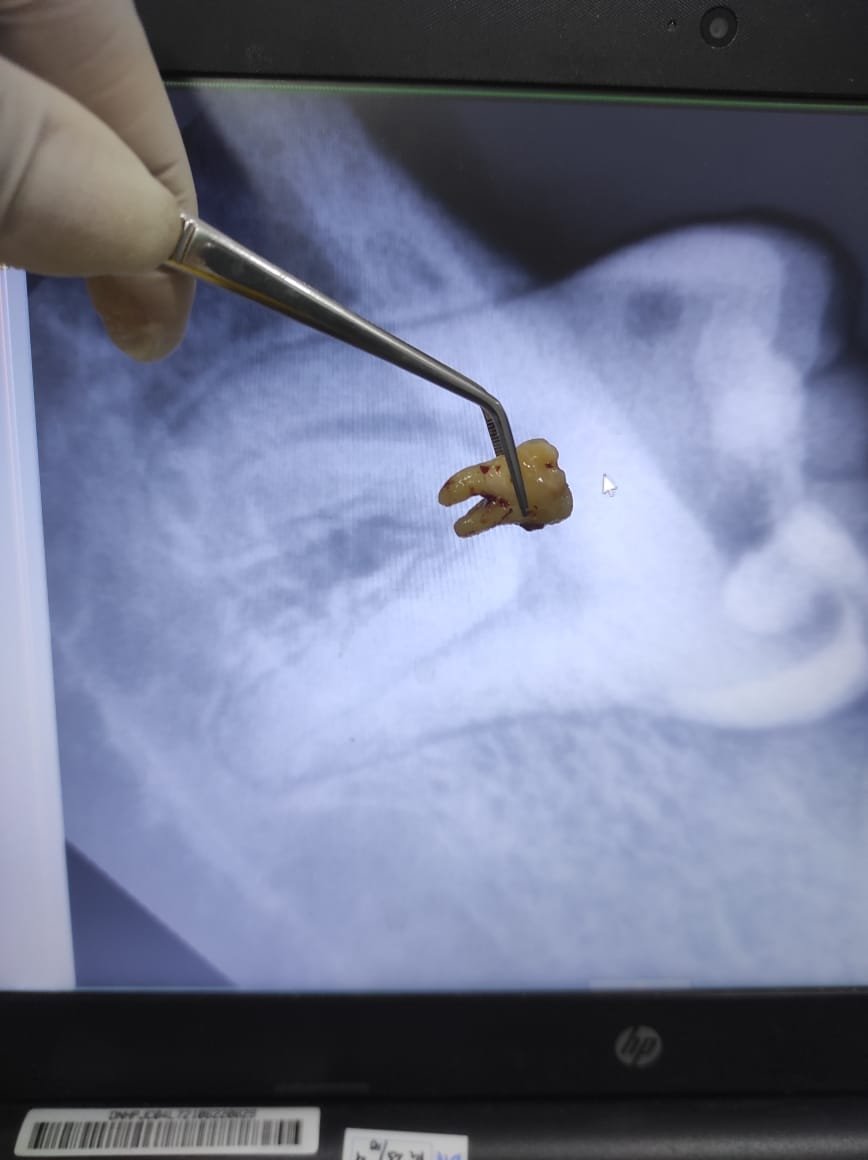

4. Pengangkatan gigi

Bila gigi sulit dicabut, dokter membaginya menjadi beberapa bagian lalu mengangkat potongan satu per satu.

After dari Cabut Gigi Bungsu